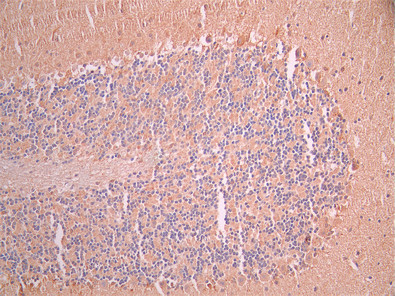

IHC image of CSB-RA859102MA1HU diluted at 1:50 and staining in paraffin-embedded mouse brain tissue performed on a Leica BondTM system. After dewaxing and hydration, antigen retrieval was mediated by high pressure in a citrate buffer (pH 6.0). Section was blocked with 10% normal goat serum 30min at RT. Then primary antibody (1% BSA) was incubated at 4°C overnight. The primary is detected by a Anti-Human lgG, Fcy Fragment Specific labeled by HRP and visualized using 0.05% DAB.